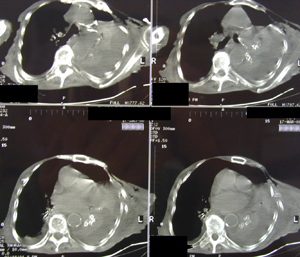

Εικόνα 1

Οπισθιοπροσθία ακτινογραφία θώρακος με πλήρη κατάληψη του αριστερού ημιθωρακίου από αίμα μετά από πτώση.